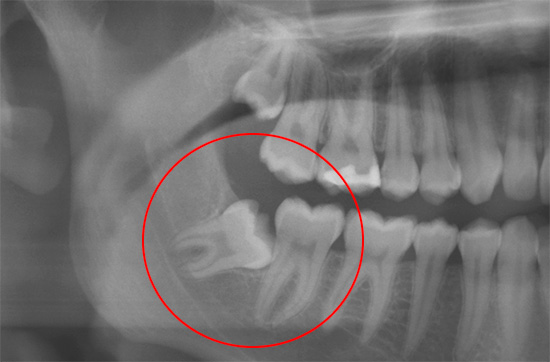

Infatti, il mal di denti a volte può dare alla testa, provocando in tal modo un'emicrania grave. Tipicamente, tali dolori sono di natura "sparatoria" a breve termine. Tuttavia, con i denti del giudizio in crescita "storti", che a causa della posizione impropria nella gomma danneggiano le radici dei denti vicini durante la loro crescita, il mal di testa può essere costante, diventando cronico. In tali casi, il dente del giudizio che lo provoca dovrebbe essere eliminato il più presto possibile, dopo di che il mal di testa passa rapidamente.

È vero che i denti malati superiori provocano un naso che cola cronico?

Poche persone sanno che la sinusite è spesso provocata da denti cattivi o un'infezione residua in canali mal trattati. Ecco perché i medici ENT chiedono sempre una radiografia e guardano le radici dei denti superiori, vicino al seno mascellare. Qualsiasi dente malato superiore che viene dopo il canino (il terzo dente) può causare il problema, ma molto spesso si tratta di premolari (quarto e quinto) e primo molare (sesto). Spesso, un naso che cola cronico scompare immediatamente dopo aver trovato e trattato un dente così malato.